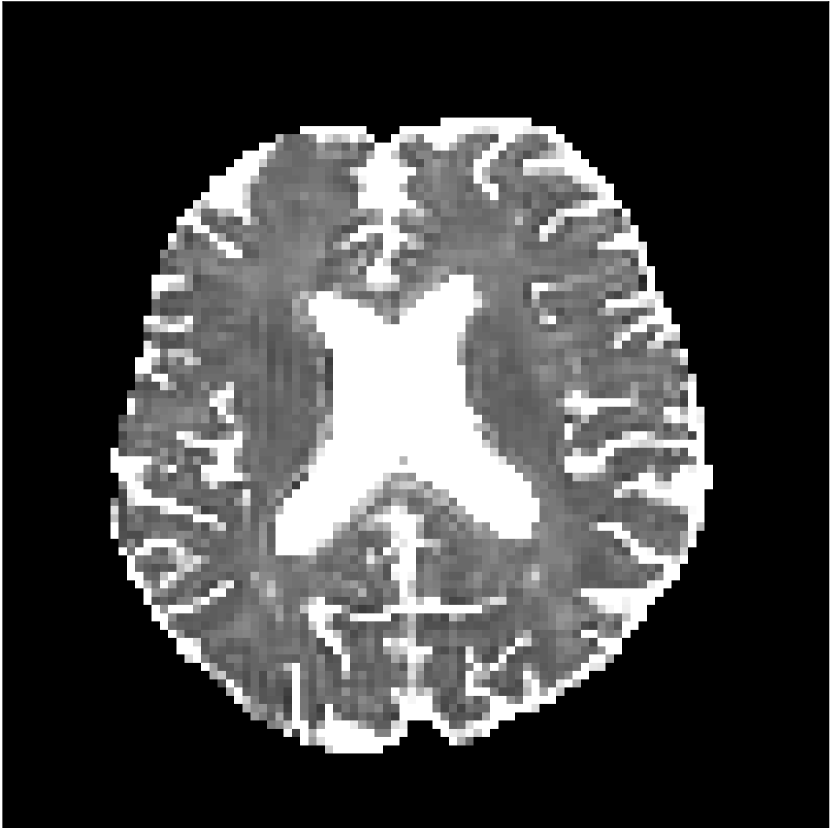

Figure 8 shows examples of non-diffusion-weighted images before and after processing. The raw images (Raw) served as the input for the magnitude deep learning (MCNN) and complex deep learning (CCNN) methods.

Raw 𝐱tsubscript𝐱𝑡\mathbf{x}_{t}

MCNN, fθ^(𝐱t)subscript𝑓^𝜃subscript𝐱𝑡f_{\hat{\theta}}\left(\mathbf{x}_{t}\right)

MCNN Resid., Ric(𝐱t)fθ^(𝐱t)Ricsubscript𝐱𝑡subscript𝑓^𝜃subscript𝐱𝑡\text{Ric}(\mathbf{x}_{t})-f_{\hat{\theta}}\left(\mathbf{x}_{t}\right)

CCNN, fθ^(𝐱t)subscript𝑓^𝜃subscript𝐱𝑡f_{\hat{\theta}}\left(\mathbf{x}_{t}\right)

CCNN Resid., Ric(𝐱t)fθ^(𝐱t)Ricsubscript𝐱𝑡subscript𝑓^𝜃subscript𝐱𝑡\text{Ric}(\mathbf{x}_{t})-f_{\hat{\theta}}\left(\mathbf{x}_{t}\right)

No PF

5/8 PF

Figure 8: Examples of non-diffusion-weighted images from in vivo data at b=0𝑏0b=0 s/mm2. Artifacts in the Raw image, 𝐱tsubscript𝐱𝑡\mathbf{x}_{t}, are corrected by the MCNN and CCNN models, fθ^(𝐱t)subscript𝑓^𝜃subscript𝐱𝑡f_{\hat{\theta}}(\mathbf{x}_{t}). Also shown are the residuals between the CNN corrections and the original Raw image with Rician bias correction Ric(𝐱t)Ricsubscript𝐱𝑡\text{Ric}(\mathbf{x}_{t}) [10]. The Gibbs artifacts removed by the methods are observed in the residuals. The MCNN method introduces some banding artifacts at the PF 5/8ths factor that are not present in the CCNN method.

Both methods remove artifacts, but the MCNN method allows residual rippling artifacts to pass through in the presence of partial Fourier. These rippling artifacts are not present in the CCNN method.